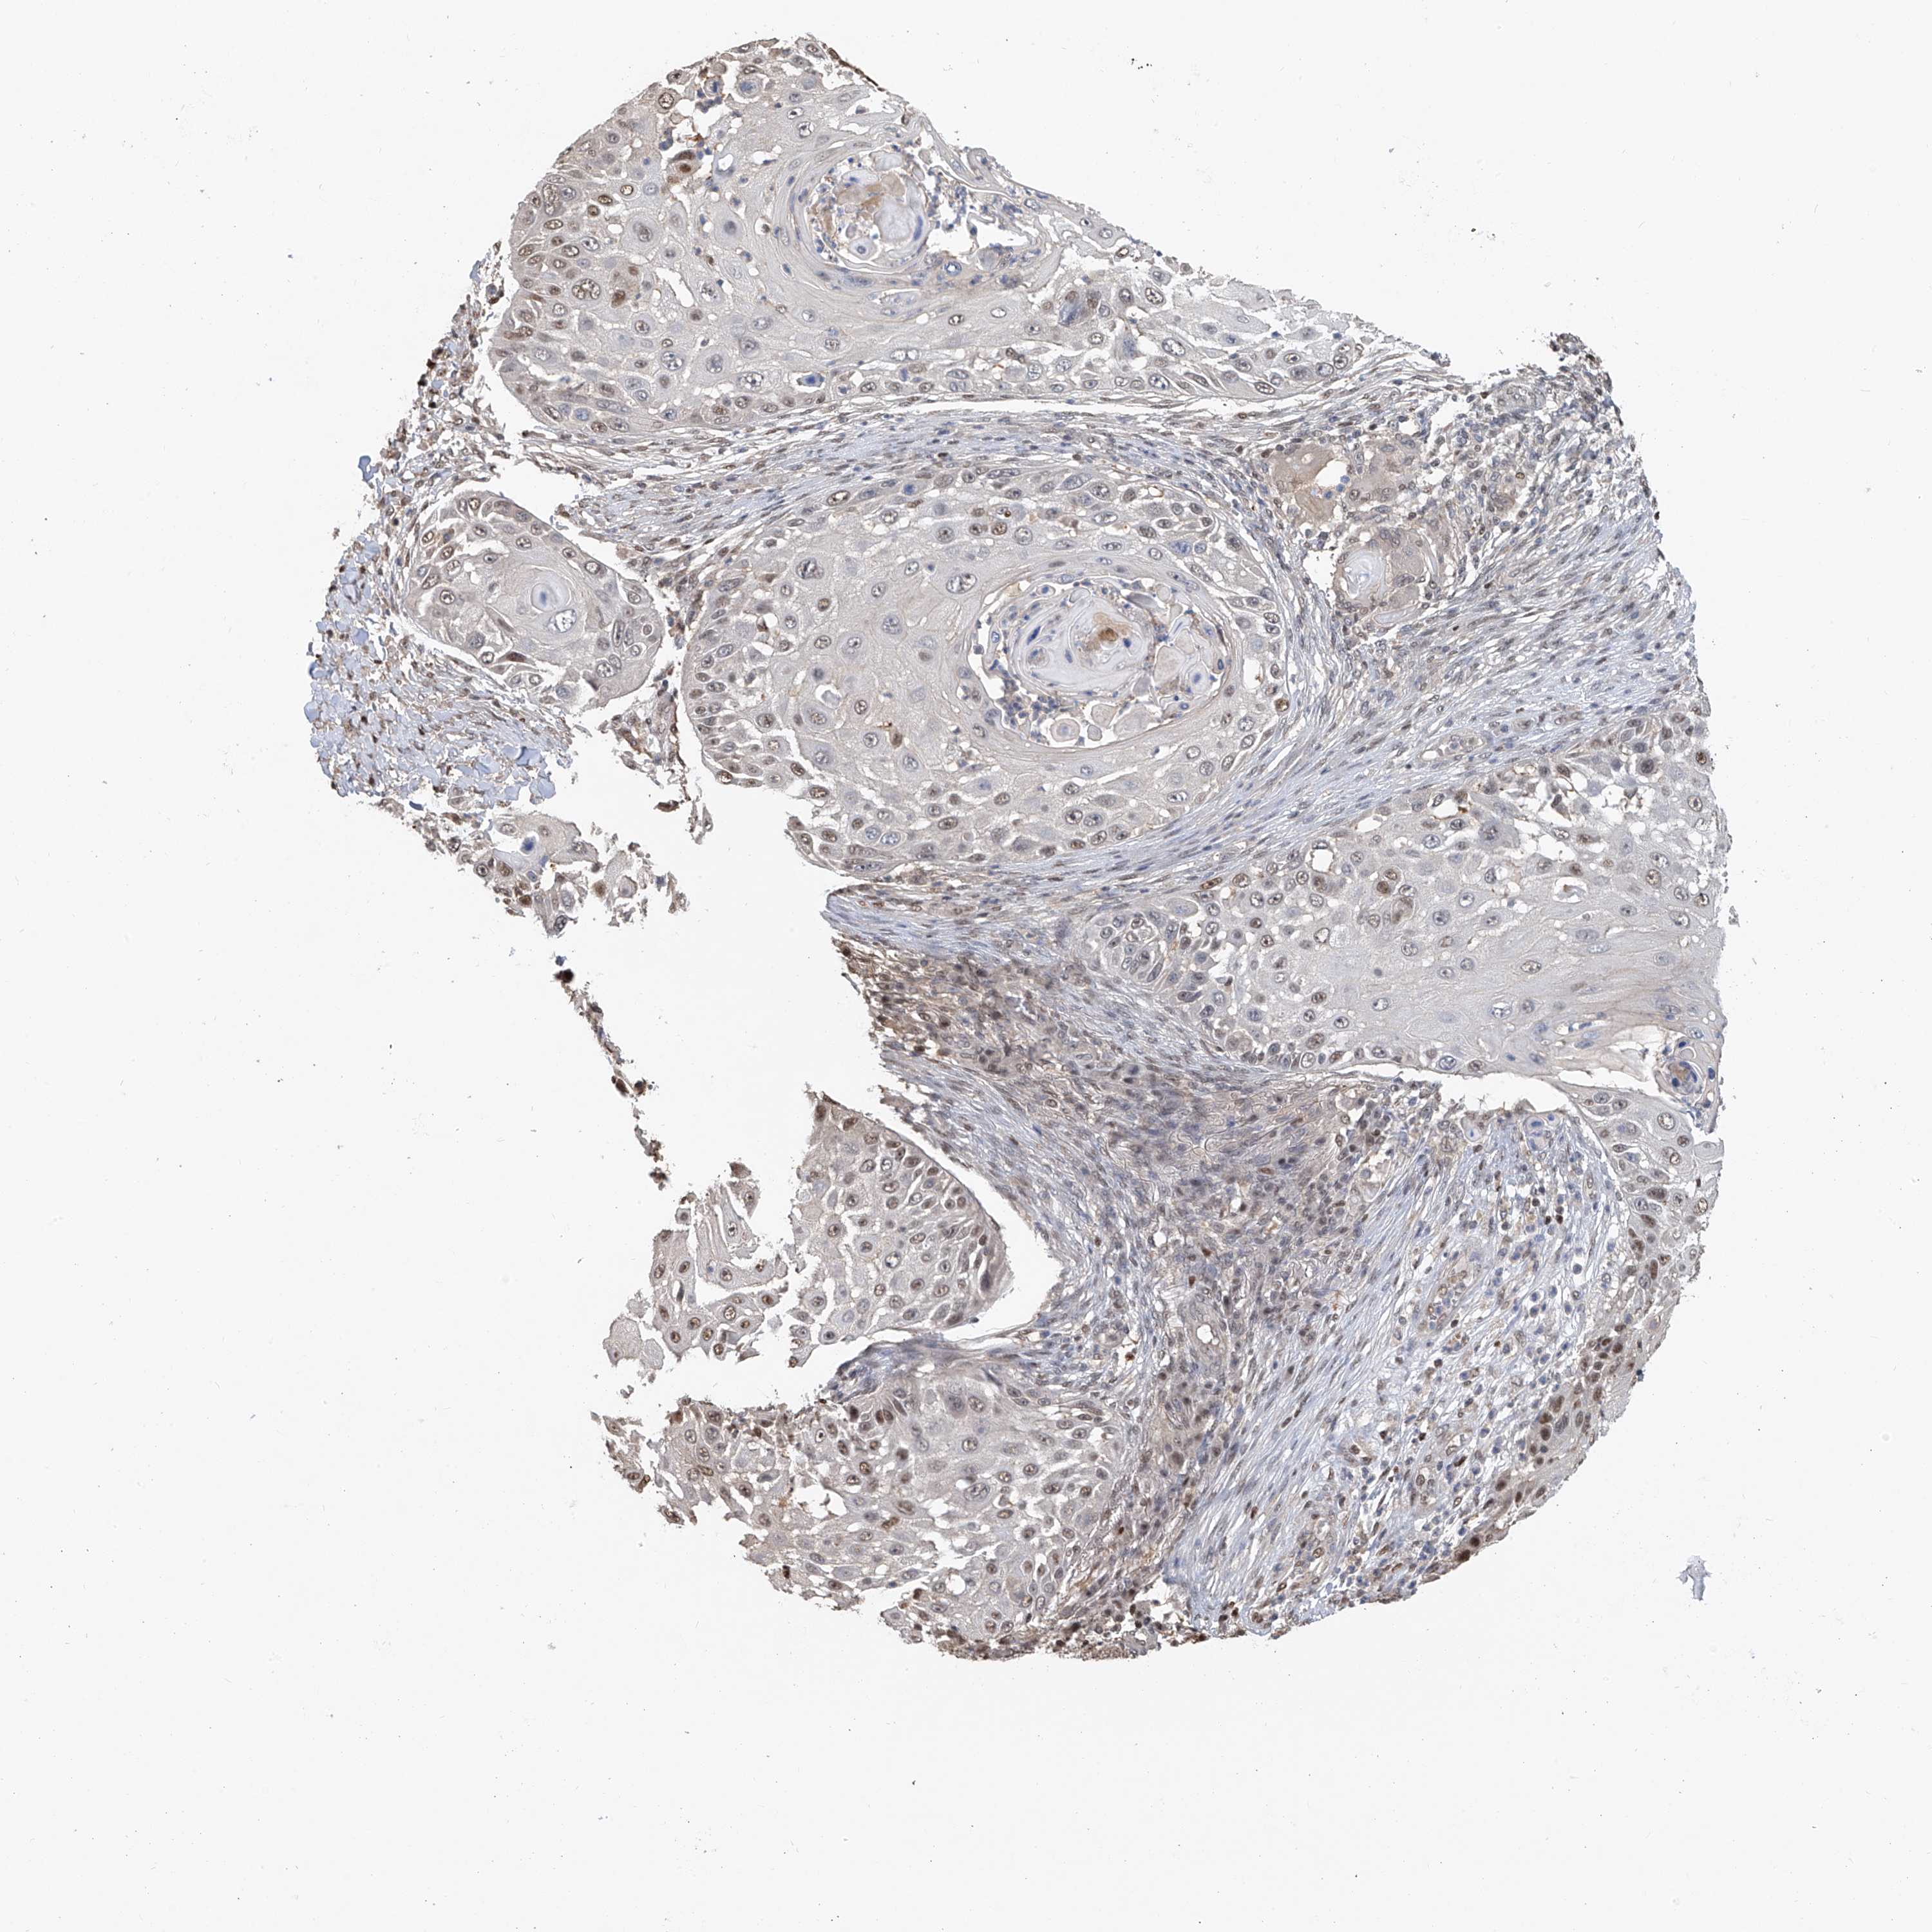

SKIN CANCER - Protein expressioni

A mouse-over function shows sample information and annotation data. Click on an image to view it in a full screen mode. Samples can be filtered based on level of antibody staining by selecting one or several of the following categories: high, medium, low and not detected. The assay and annotation is described here.

Antibody stainingi

Antibody staining in the annotated cell types in the current human tissue is reported as not detected, low, medium, or high, based on conventional immunohistochemistry profiling in selected tissues. This score is based on the combination of the staining intensity and fraction of stained cells.

Each image is clickable and will lead to virtual microscopy that enables deeper exploration of all samples and also displays staining intensity scores, fraction scores and subcellular localization as well as patient and tissue information for each sample.

Antibody HPA030712

Squamous cell carcinoma, NOS

Squamous cell carcinoma, metastatic, NOS